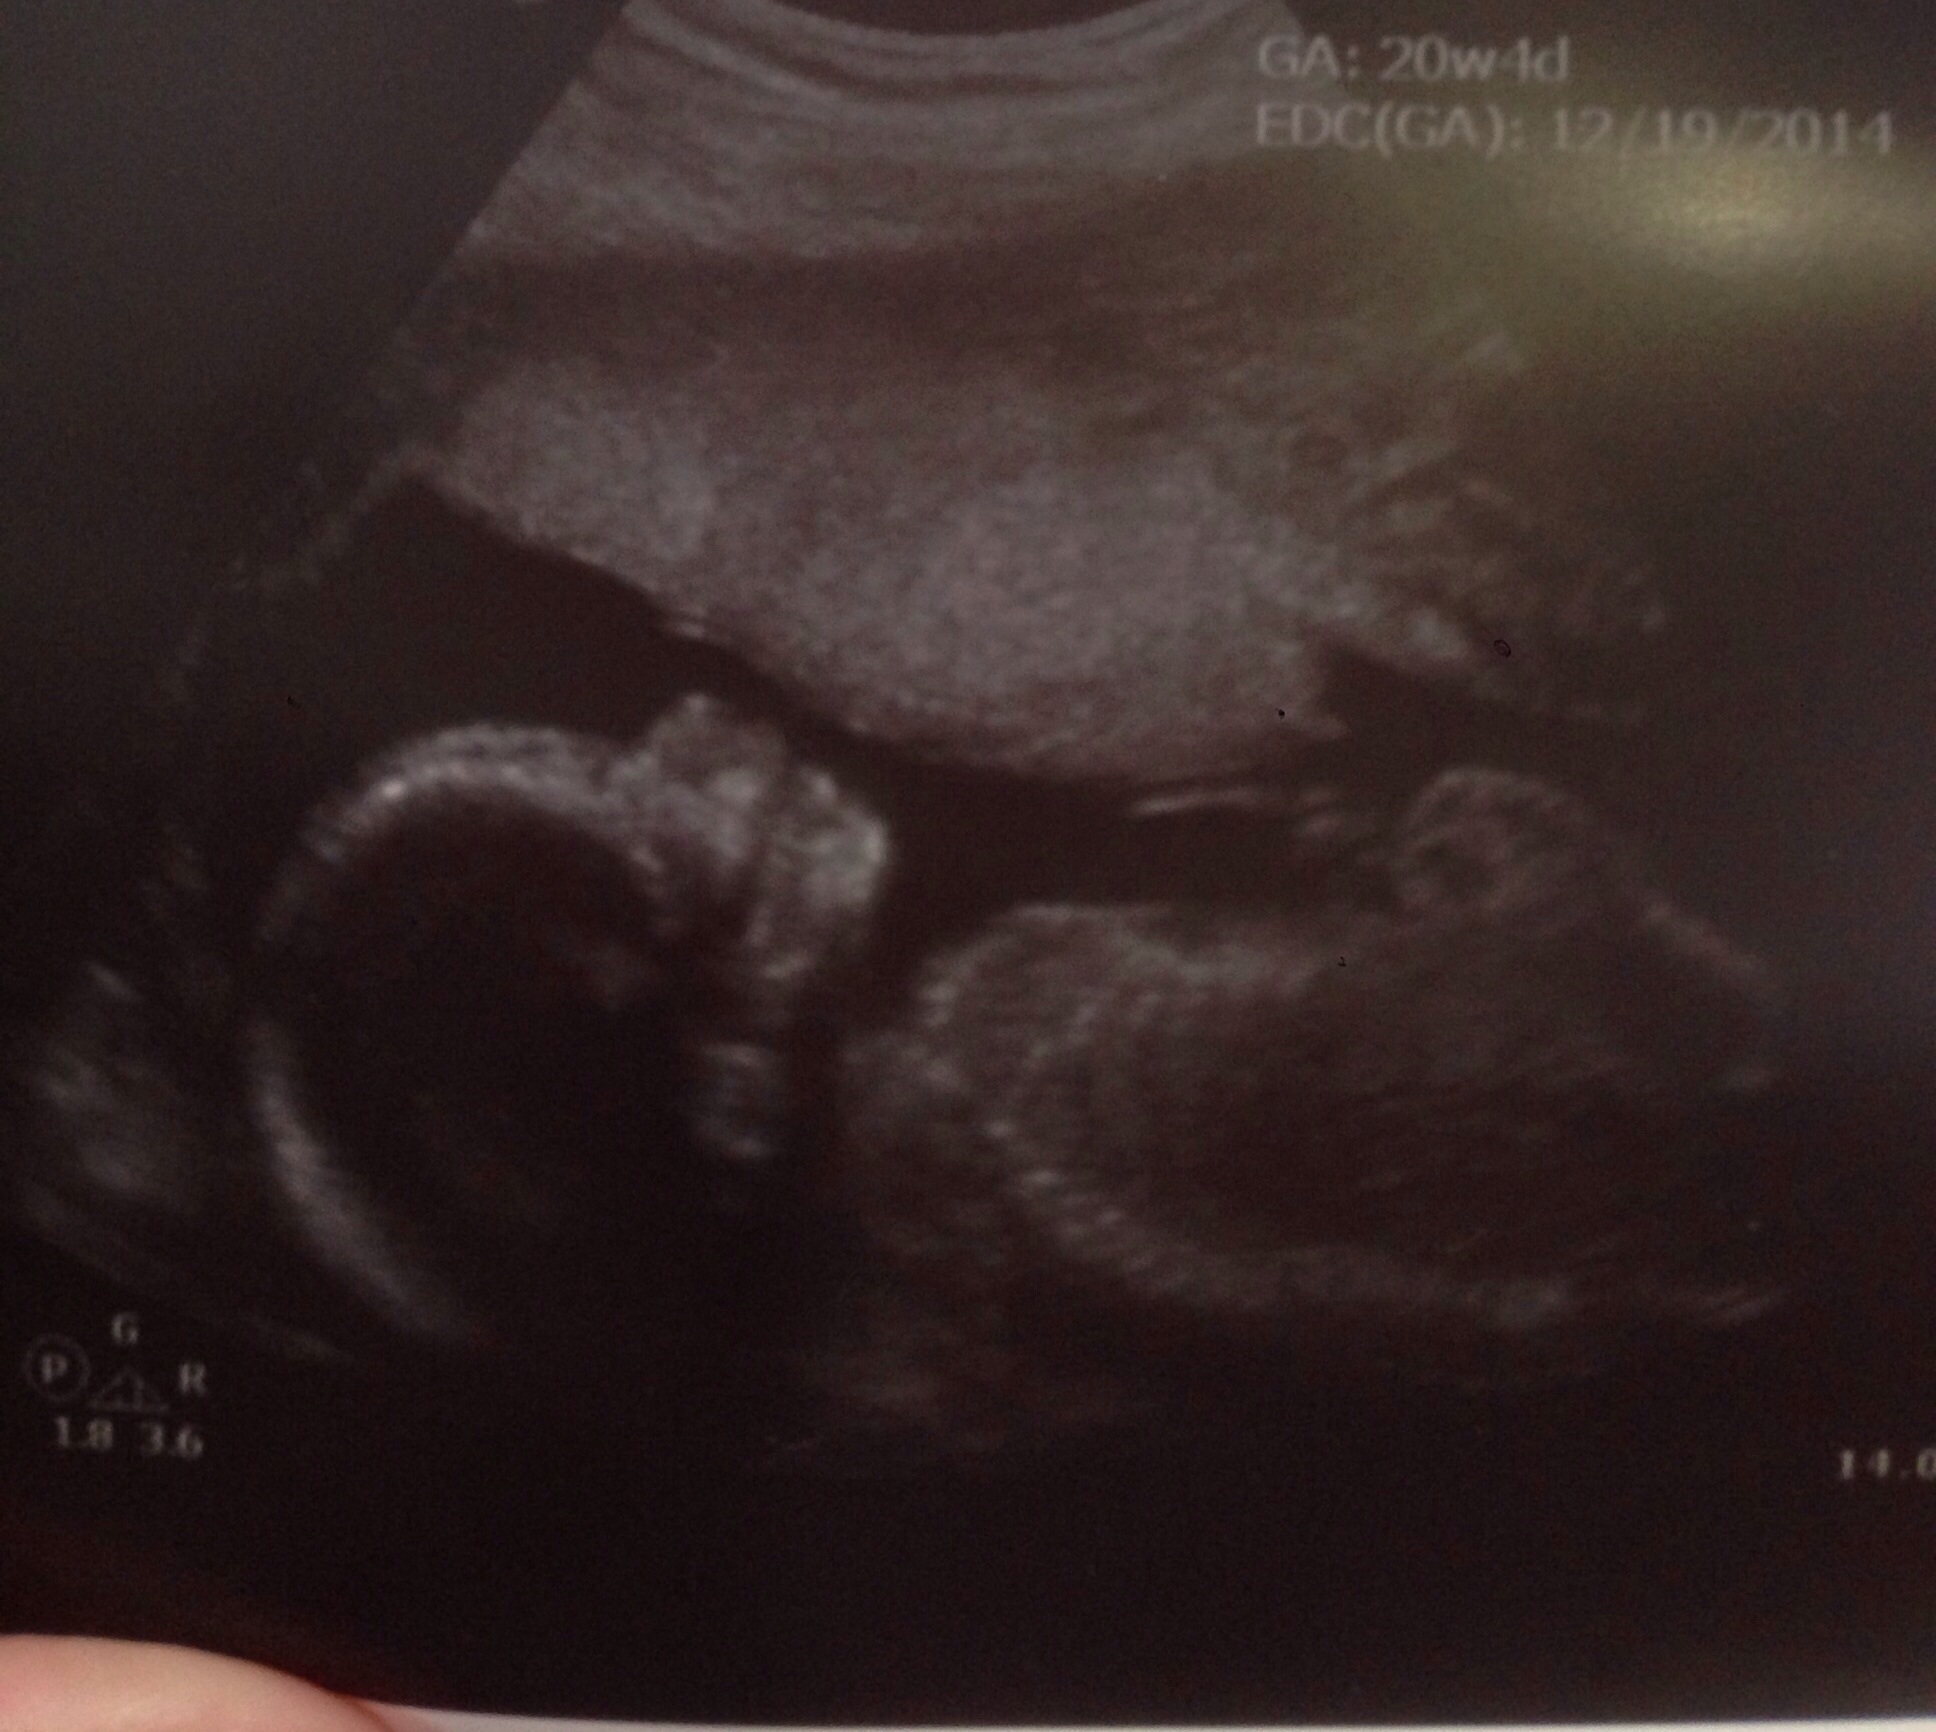

It is worth it! I just couldn't keep it all in! Yesterday was my birthday. My mom came 3.5 hrs and we spent the day buying baby clothes. Our crib also came in, so we got to put that together as well! Today, we had our a/s and our LO looks great weighing in at 13 oz! DH and I had our moms there to see the u/s as well, it was just so awesome! The tech found the sex which we have sealed in an envelope (we looked away). On Saturday, we are having a baby reveal, with 40+ confirmed guests. I know a lot of you hate the idea of a reveal party, but with DH having cancer this baby wasn't ever supposed to happen, so the fact that it's coming is something that has a lot of our family and friends very excited! Plus I've been feeling LO more and more, which is the icing on the cake!